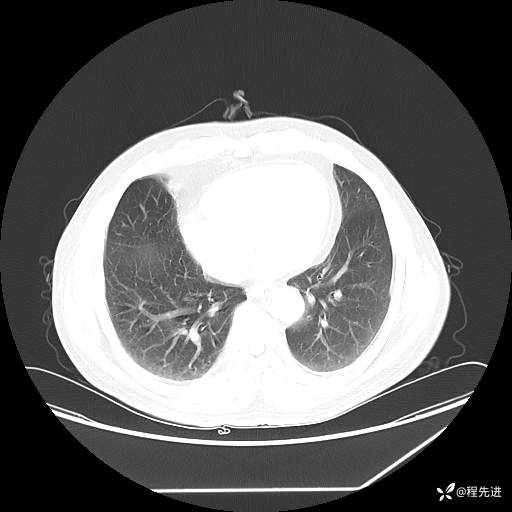

患者性别:男

患者年龄:57岁

简要病史:声嘶2月余

CT平扫+增强: